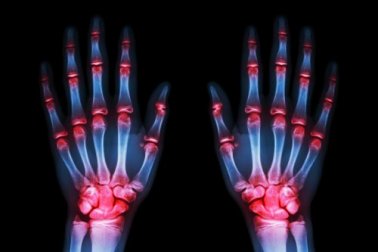

L’artrosi colpisce nel 52% dei casi le donne e solo nel 29% dei casi gli uomini. Comincia a dare i primi sintomi ad un’età compresa tra i 54 e i 60 anni e, in generale, segue questo schema:

- L’artrosi più comune colpisce le mani (70% dei casi)

- Al secondo posto troviamo i piedi (40% dei casi)

- Le altre zone più colpite sono: le ginocchia e le anche (rispettivamente il 10% e il 3% dei casi)